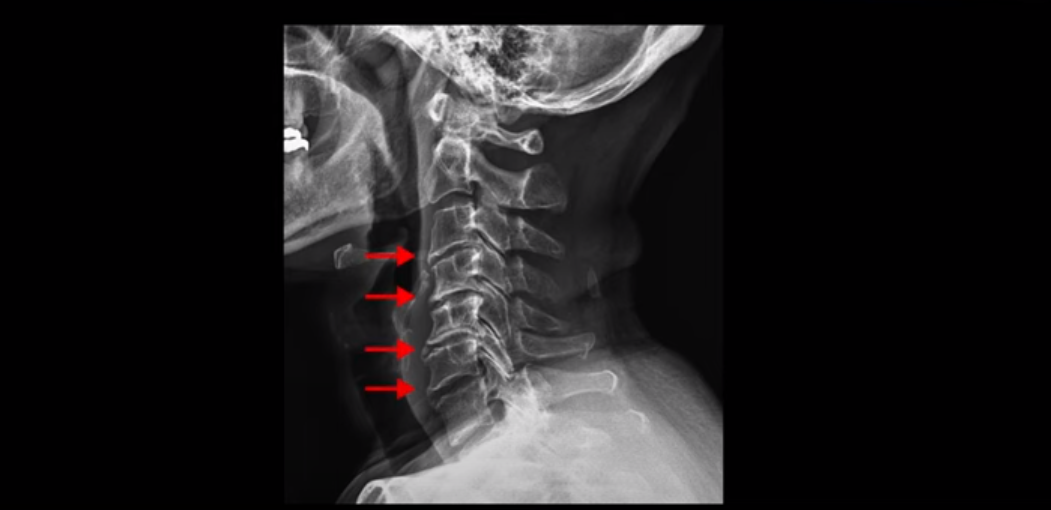

X-ray 보시다시피 완전 일자목 거북목에다 여러 마디가 전부 다 퇴행이 심하며

뼈 모양의 변형도 매우 심합니다.

X-ray로 봐도 신경 구멍들이 좁아진 게 보입니다.

이런 걸 협착이라고 부르는 거죠. 이 분의 가장 불편한 증상은 20년간 아픈 만성적인 목통증과 어깨통증, 두통과 눈 통증인데 최근 들어 가증 불편한 증상은 목이 아예 돌아가지 않는 겁니다. 그래서 운전할 때도 사이드 미러를 보려면 몸을 돌리셨다고 하는데요. 주사 효과도 전혀 없고 대학병원에서도 디스크와 협착인데 그냥 약먹고 운동만 하라고 하면 이 환자는 어떻게 해야 할까요?

이 환자분도 아까 X-ray에서 보여드렸듯이 아주 심한 일자목, 거북목이 있고 그 결과로 목의 거의 모든 마디가 다 퇴행이 진행되어 있죠. 즉 거북목은 모든 목질환, 특히 목디스크, 목협착증의 어머니 질환이며 그래서 목디스크를 치료하기 위해서는 반드시 거북목 때문에 짧아지고 뭉치고 굳고 뒤틀린 목 주변 근육들을 잘 치료해줘야 합니다.